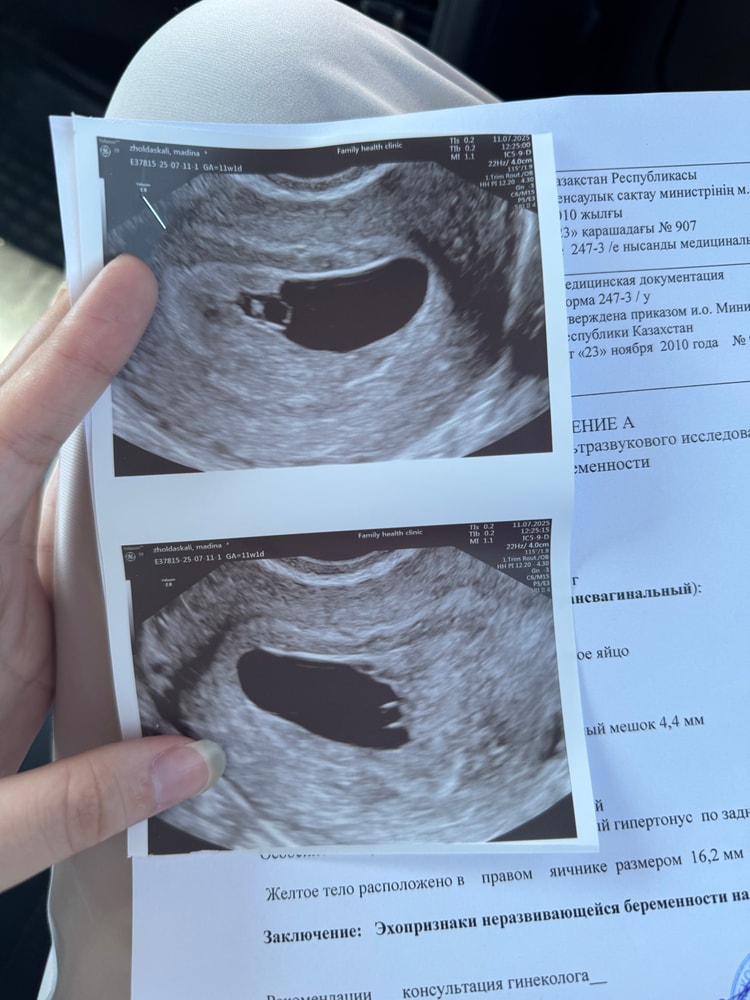

Всем доброго дня! Сегодня была на узи, узнала, что жду двойню! Очень рада, но одновременно прибавилась куча переживаний. На данный момент акушерский срок 6+1, по узи 5+6. Сердцебиение определяется у обоих эмбрионов, ктр 2,9, желточные мешочки есть. Хорион кольцевидный. Монохориальная диамниотическая двойня. На прием иду 21 июля. У кого было аналоги